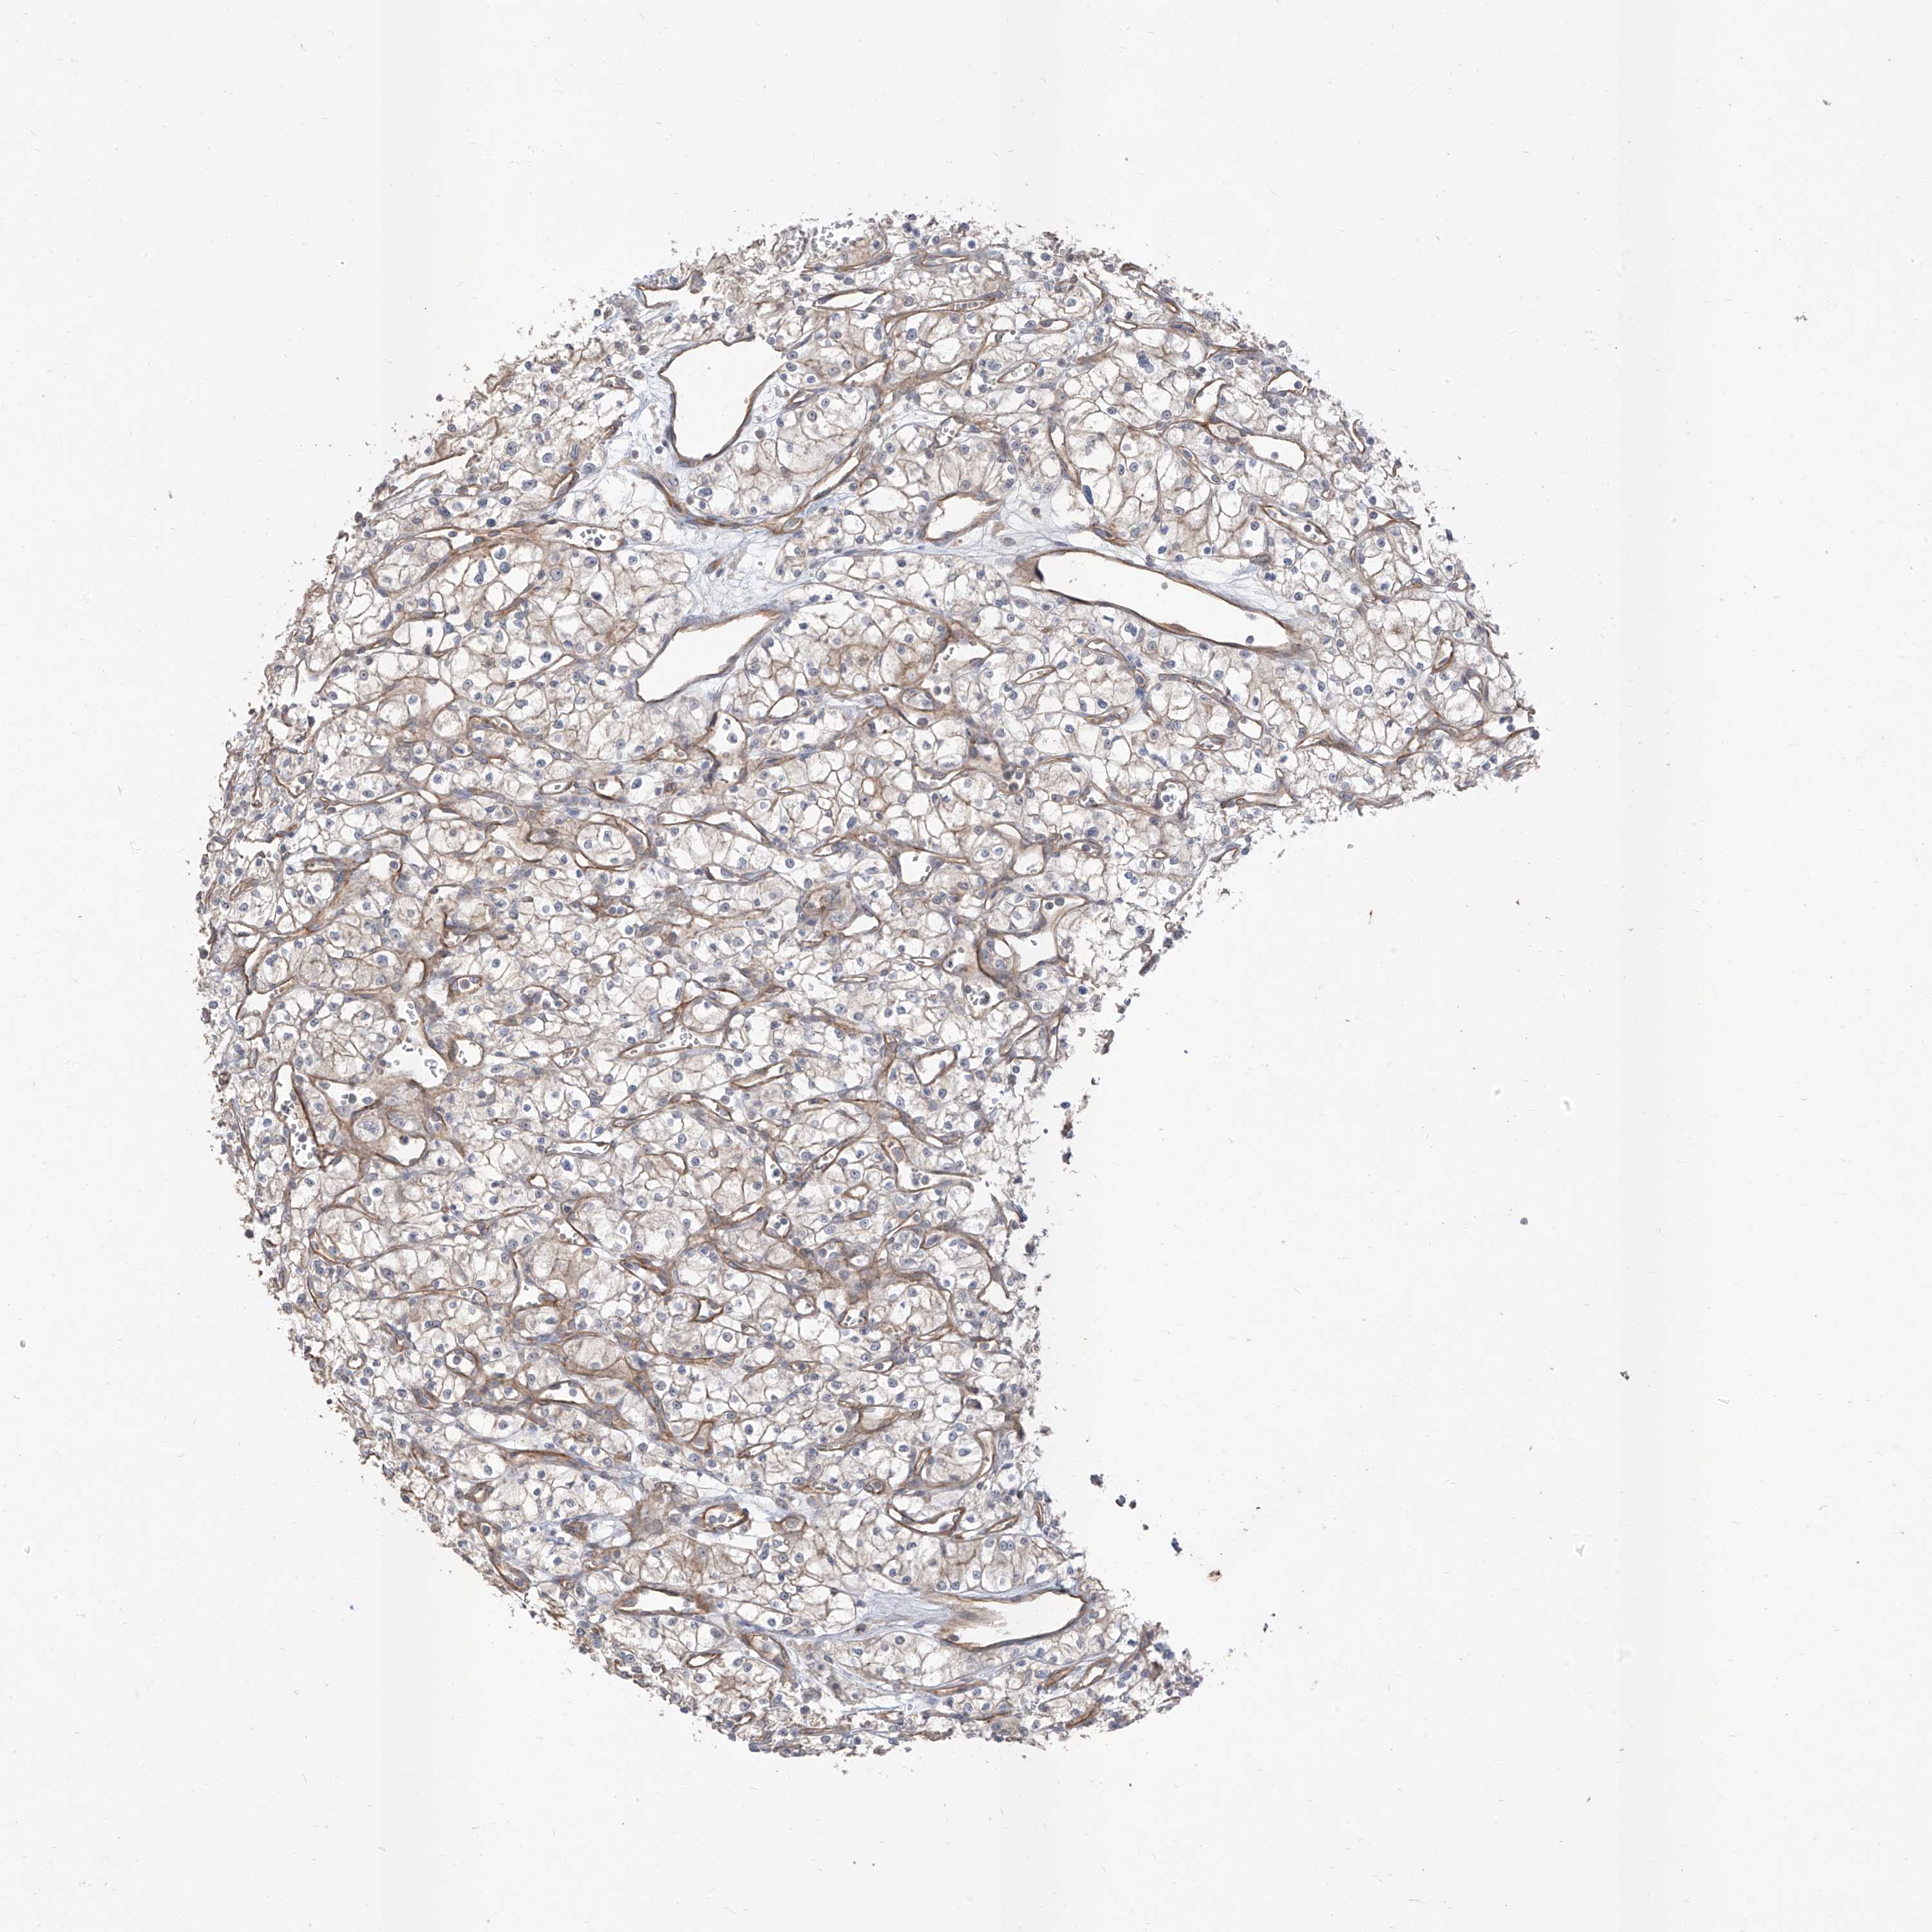

KICH TCGA KIRC TCGA KIRC VALIDATION KIRP TCGA PROTEIN RCC CPTAC PROTEIN EXPRESSION

Kidney chromophobe

KIDNEY CHROMOPHOBE (TCGA) - Interactive survival scatter ploti

The Survival Scatter plot shows the clinical status (i.e. dead or alive) for all individuals in the patient cohort, based on the same data that underlies the corresponding Kaplan-Meier plots. Patients that are alive at last time for follow-up are shown in blue and patients who have died during the study are shown in red.

The x-axis shows the expression levels (FPKM) of the investigated gene in the tumor tissue at the time of diagnosis. The y-axis shows the follow-up time after diagnosis (years). Both axes are complimented with kernel density curves demonstrating the data density over the axes. The top density plot shows the expression levels (FPKM) distribution among dead (red) and alive patients (blue). The right density plot shows the data density of the survived years of dead patients with high and low expression levels respectively, stratified using the cutoff indicated by the vertical dashed line through the Survival Scatter plot. This cutoff is automatically defined based on the FPKM cutoff that minimizes the p-score. The cutoff can be changed by dragging the vertical line or by entering a cutoff value in the square labeled "Current cut-off".

Under the Survival Scatter plot the p-score landscape (black curve; left axis) is shown together with dead median separation (red curve; right axis). Dead median separation is the difference in median mRNA expression between patients who have died with high and low expression, respectively. It is calculated as follows: median FPKM expression of dead patients with high expression - median FPKM expression of dead patients with low expression. This is intended to aid the user in visually exploring custom cutoffs and the associated p-scores and dead median separation.

Individual patient data is displayed and can be filtered by clicking on one or more of the category buttons on the top of the page. Categories describing expression level and patient information include: high, low, alive, dead, female, male and tumor stages. The scale of the x-axis can be toggled between linear and log-scale by clicking on the "x log" button. Mouse-over function shows TCGA ID, patient information and mRNA expression (FPKM) for each patient.

& Survival analysisi

Kaplan-Meier plots summarize results from analysis of correlation between mRNA expression level and patient survival. Patients were divided based on level of expression into one of the two groups "low" (under cut off) or "high" (over cut off). X-axis shows time for survival (years) and y-axis shows the probability of survival, where 1.0 corresponds to 100 percent.

EPHX4 is not prognostic in Kidney Chromophobe (TCGA)